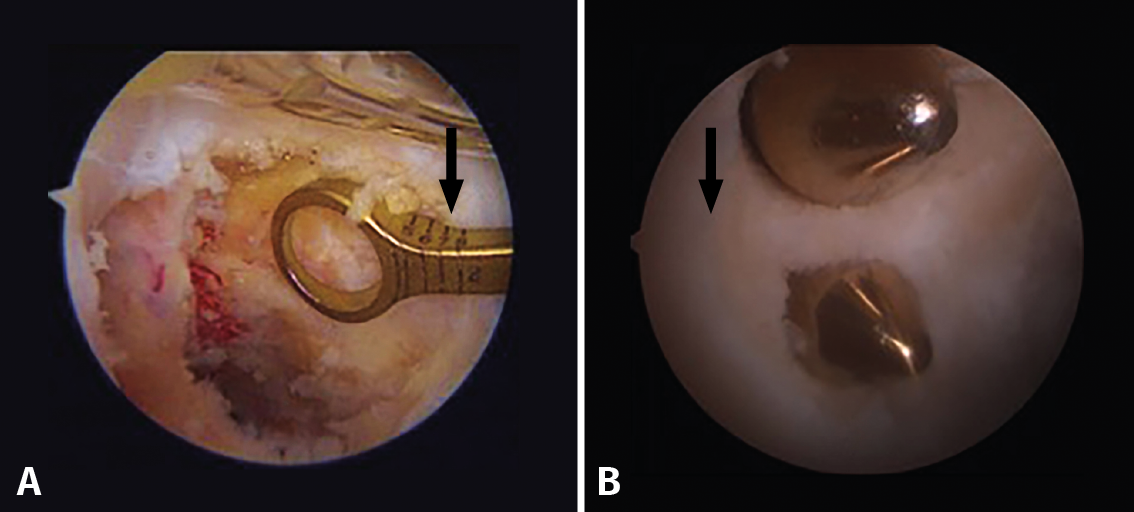

In the case of single bundle reconstructions, we should seek to position the tunnel at the centre of the two original insertion sites, with a slight tendency to reproduce the AL bundle, which is anatomically more consistent and mechanically more resistant. In the case of double bundle reconstructions, the originally described technique contemplates an 11-mm tunnel at the level of the AL bundle insertion site and a 7-mm tunnel at the PM bundle insertion site, leaving a minimum 2-mm bone bridge between the two of them (Figure 11)(28).

Figure 11. A: single bundle reconstruction. The outside-in drilling guide indicates how many millimetres the femoral tunnel is being positioned from the chondral margin (arrow); B: double bundle reconstruction. Note the distance from the chondral margin (arrow) and the bone bridge between the two tunnels.